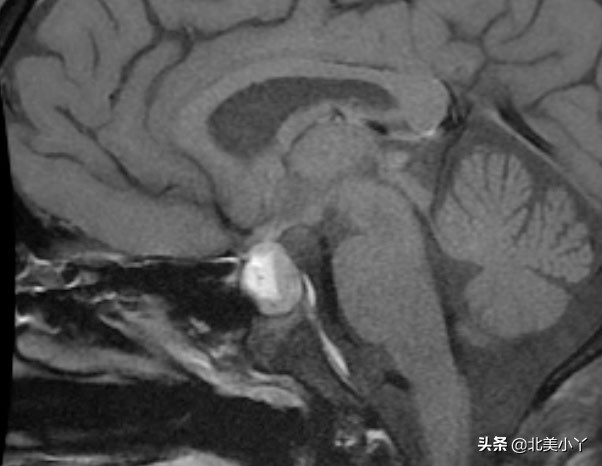

哪些医学方法可以判断得了”蝶鞍邂逅瘤“?

- 神经影像学检查,包括脑CT、垂体加强MRI。

- 手术中取肿瘤组织进行冰冻病理组织学分析——明确诊断。